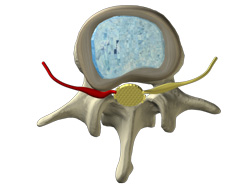

Sciatic leg pain is pain typically caused by a lumbar spine disc condition in the low back that puts pressure on a spinal nerve root which supplies messages to your legs and feet. Granted, some of us deal with pain better than others, but sciatica that travels down the leg, into the foot, and maybe even into the toes, wears on even the toughest person. All you want is relief. That is the point when thoughts often turn to surgery to relieve the leg pain sciatica, sometimes when they need not turn to surgery so quickly.